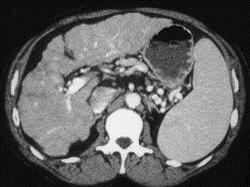

男,71岁,继往有肝炎病史,CT检查如图,请选择最佳诊断 ( )A、肝转移瘤B、肝色素沉着症C、肝癌D、肝硬化E、脂肪肝

问题 男,71岁,继往有肝炎病史,CT检查如图,请选择最佳诊断 ( )

选项 A、肝转移瘤 B、肝色素沉着症 C、肝癌 D、肝硬化 E、脂肪肝

答案 D